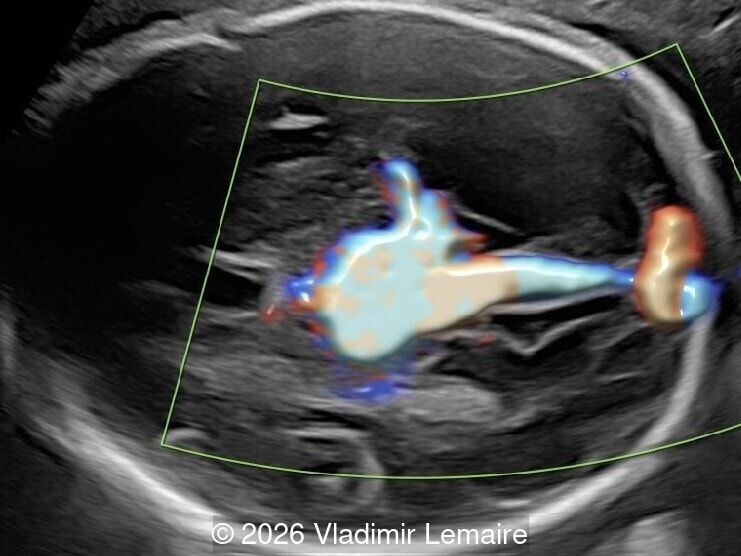

The three-vessel-trachea view with color Doppler.

Image 5 The three-vessel-trachea view with color Doppler.

Our imaging revealed enlargement of the fetal heart with dilation of the superior vena cava. On further evaluation, we identified an elongated anechoic cystic structure in the midline of the head, without mass effect on the surrounding structures. Color doppler demonstrated an arteriovenous fistula between the deep choroidal arteries and the embryonic median prosencephalic vein of Markowski. The vein of Galen aneurysmal malformation was likely the contributing factor to the cardiac enlargement. Cardiac function was, however, preserved and hydrops not present. Additional images are shown below.

On ultrasound, a VGAM appears as an elongated anechoic cystic structure in the middle of the head, often without mass effect on the surrounding structures. Color Doppler shows high-velocity flow in the lesion and can be used to identify the arteries feeding the vascular malformation. Pulsed-wave Doppler shows markedly turbulent flow. Additional key echocardiographic features include an enlarged heart with preserved systolic function, a dilated superior vena cava, and mild or moderate tricuspid regurgitation. Tricuspid regurgitation was not present in our case at the time of our evaluation.